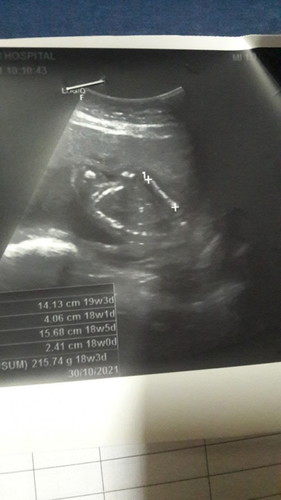

ป้าหมอบอกไม่เห็นเพศน้องหนีบขาไว้นะคะคุณแม่ เห้ออิแม่ก็อยากเห็นใจจิขาด #แต่ได้ลูกสาวชัวร์แหละ😘

บ้านนี้ก็เหมือนกันค่ะ ซาวด์ไม่เห็นลุงหมอบอกน่าจะเป็นผู้หญิง #ทีมตุลา64